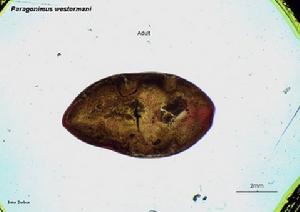

是人體並殖病主要病原。衛氏並殖吸蟲成蟲蟲體肥厚,背側稍隆起,腹面扁平。活體紅褐色,不停做伸縮運動,體型不斷變化,固定後染色蟲體在光鏡下可見體表面布滿小棘,大多為單生型。口、腹吸盤大小略同,腹吸盤約在蟲體中部。卵巢與子宮並列於腹吸盤之後,卵巢6葉,兩個睪丸分支如指狀,並列於蟲體後1/3處。卵巢類型、口、腹吸盤比例、睪丸長度比是並殖吸蟲形態鑑別重要特徵。蟲卵呈橢圓形,卵蓋大且常略傾斜。

並殖吸蟲病形態:衛氏並殖吸蟲成蟲蟲體肥厚,背側稍隆起,腹面扁平。活體紅褐色,不停做伸縮運動,體型不斷變化,固定後染色蟲體在光鏡下可見體便布滿小棘,大多為單生型,偶爾可見簇生及混生者。口、腹吸盤大小略同,腹吸盤約在蟲體中部。消化器官包括口、咽、食管及兩支彎彎曲的腸道。卵巢與子宮並列於腹吸盤之後,卵巢6葉兩個睪丸分支如指狀,並列於蟲體後1/3處。卵巢類型、口、腹吸盤比例、睪丸長度比並殖吸蟲形態鑑別重要特徵。蟲卵呈橢圓形,卵蓋大且常略傾斜。